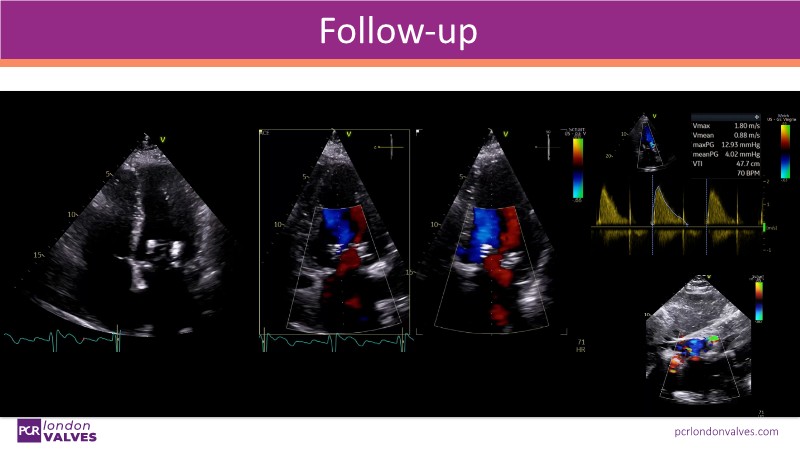

This session explores a full spectrum of therapeutic options for mitral and tricuspid regurgitation, focusing on the PASCAL Precision system for targeted repair and the SAPIEN M3 transcatheter mitral valve replacement. Through beating heart simulators, case discussions, and clinical evidence, participants will understand the versatility and unique features of these advanced interventions.